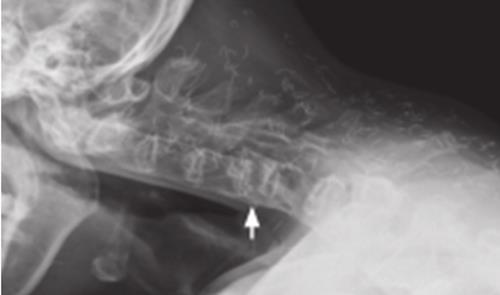

您好,强直性脊柱炎的患者如果进入中后期,用简单的X光检查就可以判断,初期的话就算是用核磁共振也一样看不出什么变化,有可能发病的时候只是髋部与积水。确切的说,如果是初期没有发病的情况下用这些常规的影响检查是查不出来什么的。如果中后期可能不做任何检查一个经验丰富的医生也能看出来是强直性脊柱炎。核磁共振是用来诊断内部器官的微小变化的仪器,对检测脑内血肿、脑外血肿、脑肿瘤、颅内动脉瘤、动静脉血管畸形、脑缺血、椎管内肿瘤、脊髓空洞症和脊髓积水等颅脑常见疾病非常有效,同时对腰椎椎间盘后突、原发性肝癌等疾病的诊断也很有效。但是强直用它有点儿牛刀的意思。基本上通过血液检查和X光片儿就可以判断此病了。您好,hal-b27是需要查一下的,强直要看看这个是不是阳性的,当然如果是阳性的话,也不一定是的,如果是阴性的,就肯定不是的了,不过医生告诉我说,如果骶髂关节核磁共振结果百分の70到80确定的话,就基本上是的了,建议你一定要到大的医院,治疗强直专业一些的医院去看看,平时生活上要多做运动,如游泳,八段锦,千万不可做剧烈的运动,我平时就是做一些简单的瑜伽动作和肚皮舞什么的,平时座要直,站也是,一定只要注意自己的体型,还有就是饮食上也要多注意,网上查查什么能吃什么不能吃,最最主要的是一定要保暖和不要疲劳,负责容易加重病情,恶化!